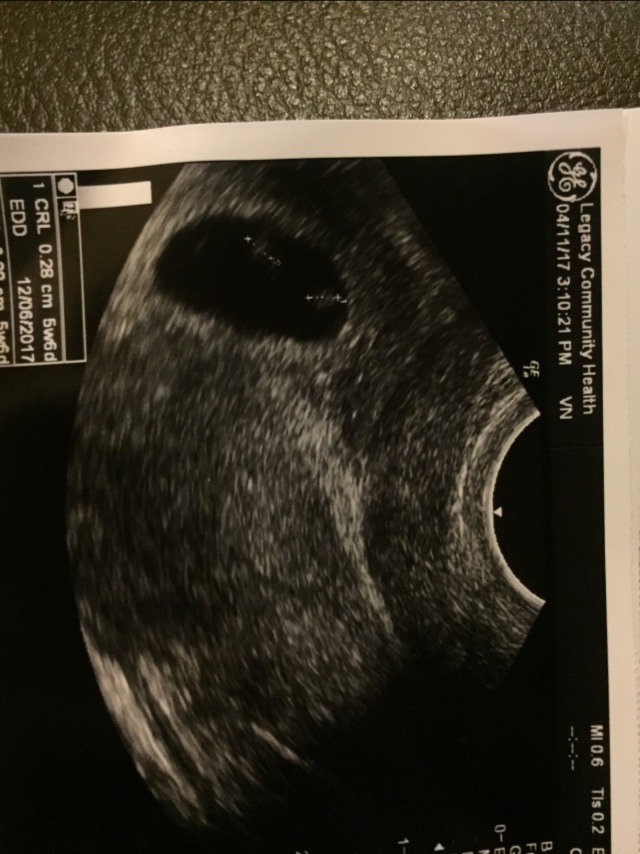

I had an ultrasound today having twins but one thing that concerned me was that my dr told me my yolk sac is big and both babies are measuring 5w 6 days should I be concerned or just relax ? Anybody else had Any experience like this ???